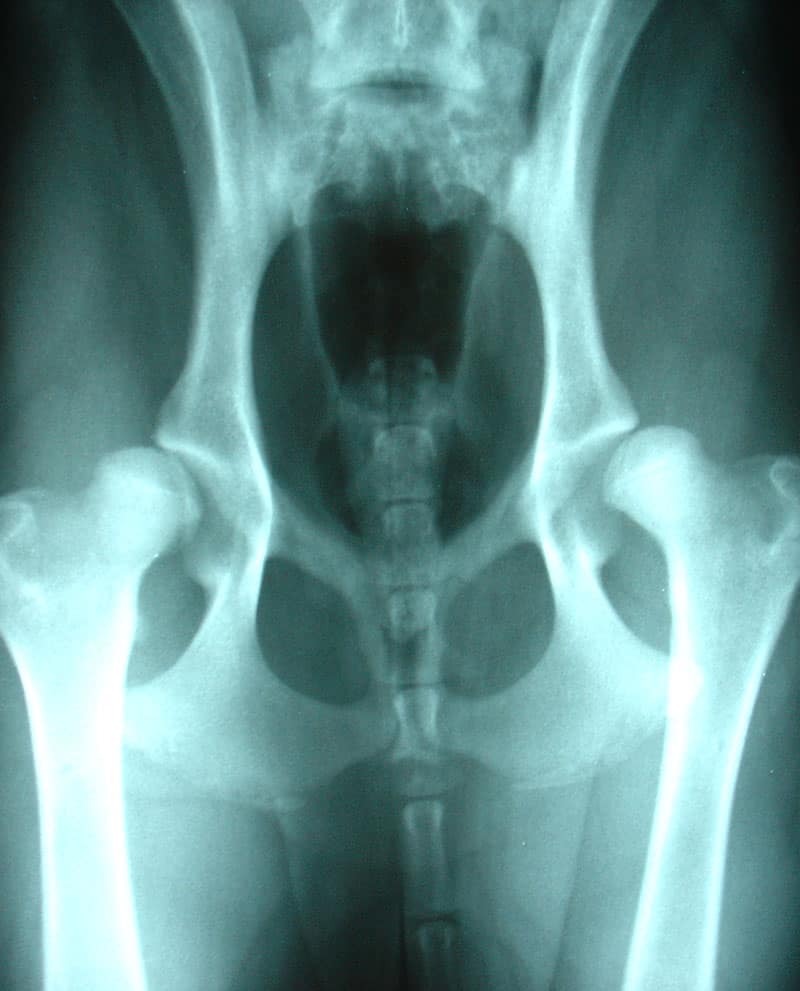

How to Treat Hip Dysplasia in Dogs

Sadly, veterinarians have no cure for hip dysplasia. This abnormality in the connection between a dog’s pelvis and thigh bones is a genetic condition—you can no more change the fact that a dog has hip dysplasia than you can change the color of his eyes.